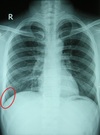

What is the red arrow indicating?

Is this a normal finding on a CXR?

A

• Gastric bubble

• This is a normal finding on a CXR

Free air: Instead of the air being contained inside the stomach to the unitlateral side of the diaphgram, air will be displaced bilaterally on both sides of the diaphragm.